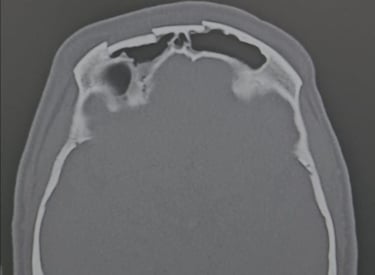

Neurotraumatologia

Tratamos casos diversos relacionados a traumatologia, como hematoma subdural crônico, hematoma subdural agudo, hemicraniectomias descompressivas por causas diversas e afundamentos cranianos abertos e complicações precoces ou tardias, como fístula liquórica, abscesso intracraniano, dentre outros